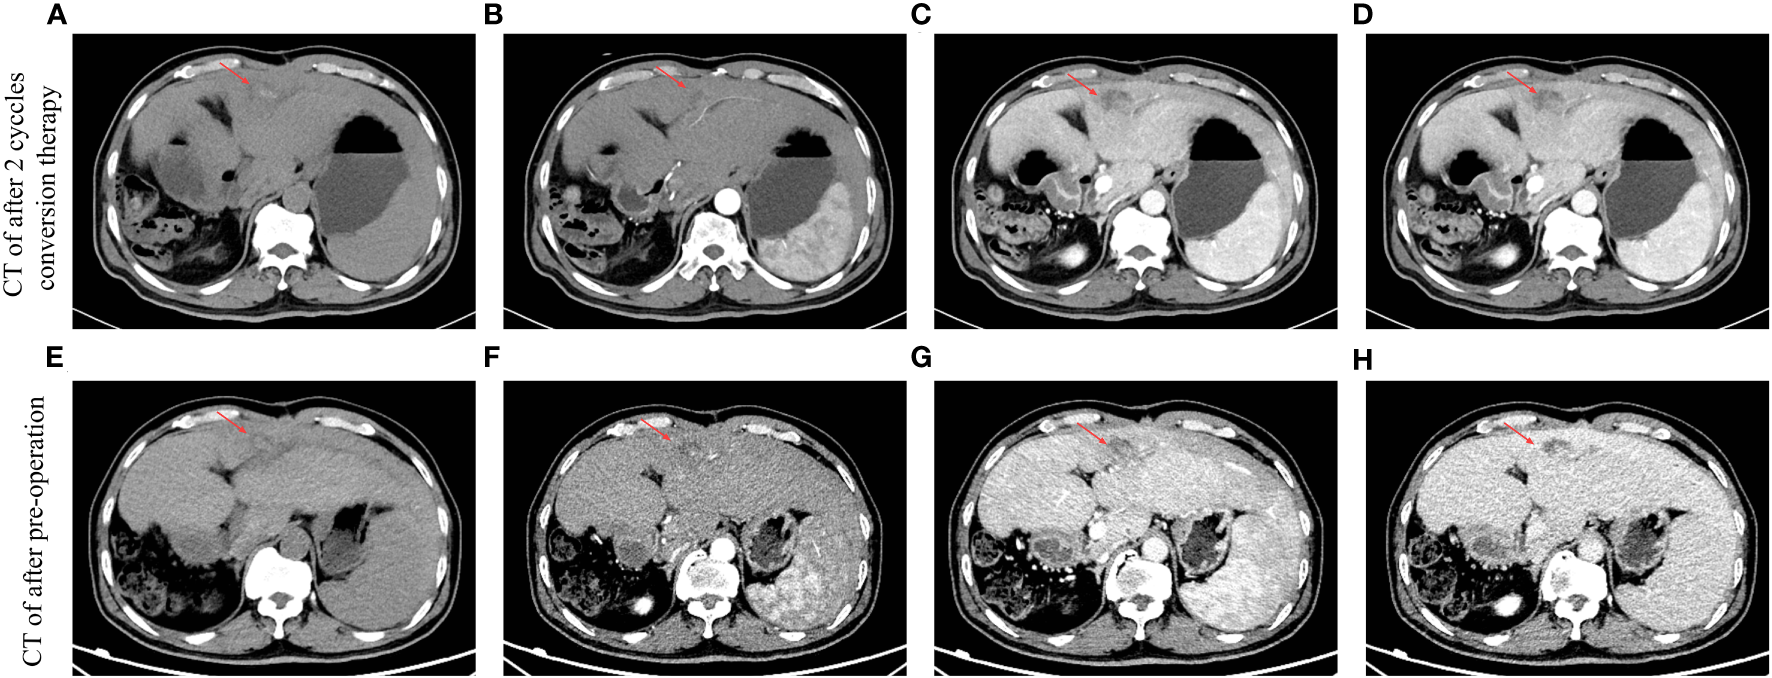

Figure 3

Results of multi-phase CT scans can be evaluated after different periods of conversion therapy. The red arrow indicates an intrahepatic tumor. (A) CT image after two cycles of conversion therapy in the period of non-contrast scan. (B) CT image after two cycles of conversion therapy in the period of the arterial phase. (C) CT image after two cycles of conversion therapy in the period of the portal vein phase. (D) CT image after two cycles of conversion therapy in the period of the delay phase. (E) CT image after preoperation in the period of non-contrast scan. (F) CT image after preoperation in the period of the arterial phase. (G) CT image after preoperation in the period of the portal vein phase. (H) CT image after preoperation in the period of the delay phase.